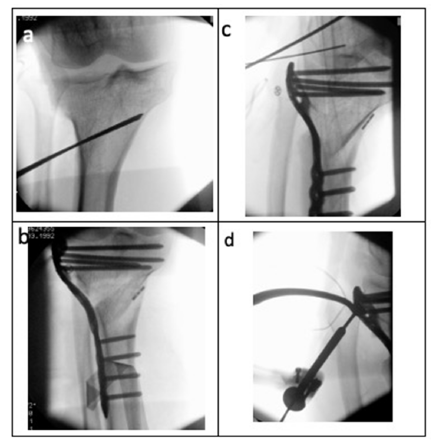

Following height marking under fluoroscopic control, an infratuberositary lateral open wedge high tibial osteotomy was executed. The osteotomy was stabilized using a locking plate and the osteotomy gap was filled with allogenic cancellous bone graft (Figure 3).

Figure 3:Intraoperative Fluoroscopic Images. a) Osteotomy height marking using two parallel inserted Kirschner wires (2.0 mm diameter). b) Osteotomy result with the fixation plate in situ. c) Marking for the Arciero reconstruction using Kirschner wires to identify the popliteal sulcus and the lateral femoral epicondyle; the implanted TightRope for stabilization of the proximal tibiofibular joint is also visible. d) Marking of the drill canal through the proximal fibula for the Arciero reconstruction using a targeting device.

After correction, anatomical realignment of the previously proximalized fibular head within the tibiofibular joint was achieved. The proximal tibiofibular joint was stabilized using a syndesmotic TightRope fixation.

Subsequently, an Arciero-type reconstruction of the posterolateral corner was performed using a peroneus longus tendon graft and a neo-capsule was created using a second peroneus longus graft. The Arciero reconstruction followed standard technique [3,4]: Fixation of the popliteus tendon graft using a SwiveLock anchor within the popliteal sulcus and fixation of the LCL limb with an interference screw. The neo-capsule was secured to the dorsolateral tibial plateau using an additional SwiveLock anchor (Figure 4).